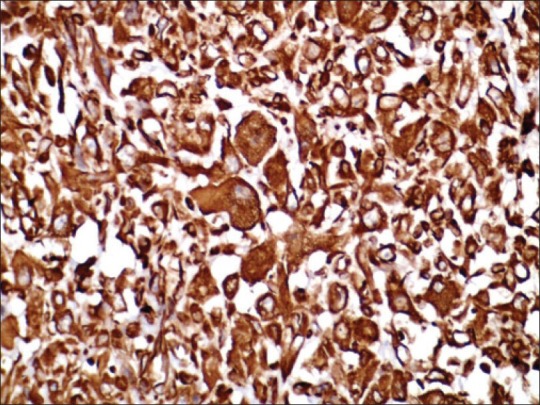

Microscopy revealed a pleomorphic malignant tumor comprised of both epithelial and mesenchymal elements. The cells were arranged in sheets, nests, and cords. Binucleated and multinucleated tumor cells were evident. Few tumor cells had abundant granular eosinophilic cytoplasm. Many abnormal mitotic figures were also noted [Figure 2]. The tumor cells were infiltrating up to the overlying skin Three of the nine axillary lymph nodes showed tumor deposits. Immunohistochemistry showed that the tumor cells were reactive for vimentin [Figure 3], desmin, and cytokeratin; and were negative for estrogen receptor (ER), progesterone receptor (PR), and Her-2/neu. Based on the above features, the tumor was diagnosed as metaplastic carcinoma with rhabdomyosarcomatous element.

| Figure 2:Photomicrograph showing pleomorphic malignant tumor comprised of both epithelial and mesenchymal elements (H and E, ×100). The inset shows tumor cells with abundant granular eosinophilic cytoplasm (H and E, 400)